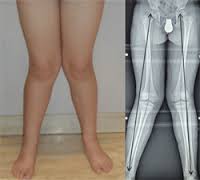

2. Piernas en X – Genu Valgo. Es una deformidad caracterizada porque el muslo y la pierna se encuentran desviados. Puede presentarse entre los 3 y los 6 años, cuando el cuerpo atraviesa un cambio natural en el alineamiento de las piernas. Casi nunca requiere tratamiento porque las piernas se suelen enderezar por sí solas. Cuando el problema es muy pronunciado, sea en las dos piernas o en una sola, se debe acudir al médico y si se presenta dolor o dificultad para caminar se puede considerar una operación correctiva después de los 10 años.

Lo importante de esto no es la estética, que nos guste más o menos la forma de las piernas, sino las consecuencias que esta forma pueda traer en el futuro sobre las rodillas, caderas y espalda. Mientras la forma de las piernas permita que la transmisión del peso desde la cadera al tobillo pase centrada por la rodilla la alineación es correcta (considerado fisiológico). Si esta transmisión de carga se realiza por fuera o por dentro de la rodilla la alineación no es correcta.